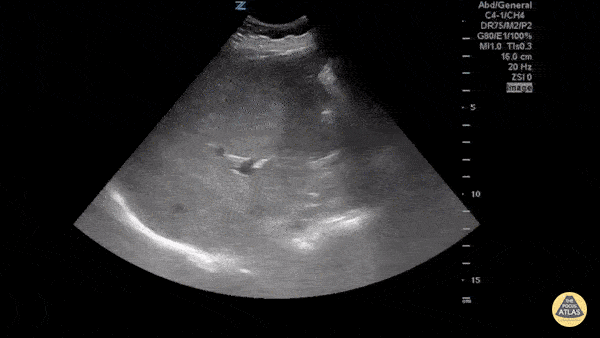

Emphysematous cholecystitis is the result of gas formation within the wall or lumen of the gallbladder as a result of infection by a gas forming organism. It is a surgical emergency. The air in the gallbladder appears highly echogenic with mild posterior shadowing, as air next to tissue is highly reflective. Sukh Singh, MD